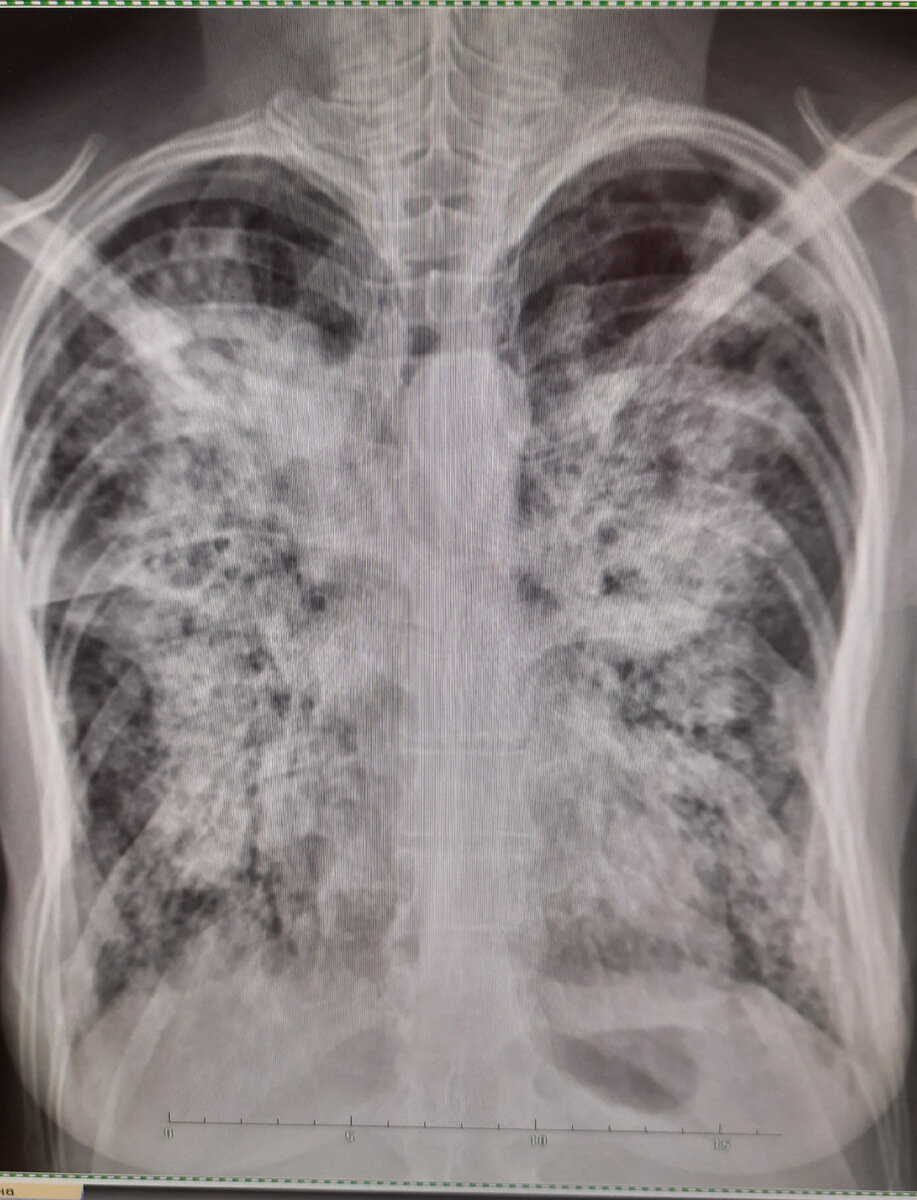

Вот такой запущенный туберкулёза выявлен у человека, который 5 лет не проходил флюорографию..

1. Среди взрослых туберкулез выявляеться методом ежегодной флюорографии. Если оценить кто подходит ежегодно флюорографию, то можно слать вывод, что это работающие граждане, или те, "кого заставили" - кто проходит мед осмотр на оружие, водительские права и пр., редко когда попадаются сознательный неофициально трудоустроенный гражданин, который пройдёт сам профилактический осмотр.. Таким образом из ежегодного профилактического осмотра на туберкулез чаще всего выпадает именно тот контингент, который ним и болеет - БОМЖИ, потребители наркотиков, зависимые от алкоголя и т.д. Эти люди делают рентгенобследование только когда состояние их здоровья совсем уже не позволяет дома заниматься самолечением, и, зачастую, при таком обращении к врачу выявляються запущенные и распространённые формы туберкулёза с массивным бактериовыделением. Такой человек за день может заразить на порядок больше людей, чем малые формы туберкулёза. Поэтому, проводя профилактические осмотры "одним и тем же" работающим гражданам мы не добьёмся эффективного выявления туберкулёза. Ну а если проблемы не видеть, то её как-бы и нет. И все хорошо.